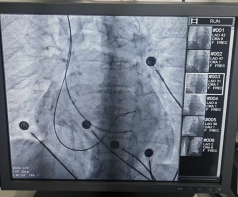

術(shù)中發(fā)現(xiàn)患者右房明顯增大,下腔靜脈增寬,三尖瓣重度返流,導(dǎo)致電極植入困難,在團(tuán)隊(duì)和導(dǎo)管室醫(yī)技人員的密切配合下,先后植入兩根主動起搏電極置于右室間隔。經(jīng)過測試電極各項(xiàng)參數(shù)良好,CCM工作發(fā)送正常,患者各項(xiàng)生命體征平穩(wěn),手術(shù)全程僅40min左右。術(shù)后檢查顯示設(shè)備運(yùn)行良好,患者生命體征平穩(wěn)。